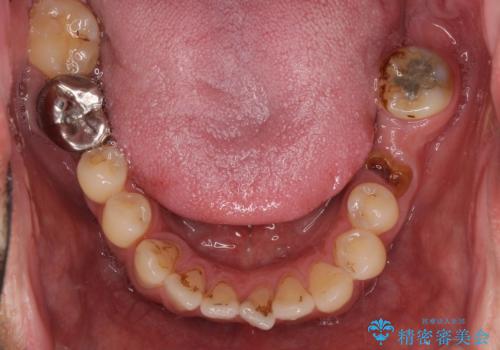

- 前歯や奥歯の虫歯を放置しており、それらの治療を契機に真っ白な歯にしたいとのことで来院された患者様です。

咬み合わせを改善するに当たって、抜歯しなければならない歯や歯列の改善が必要な箇所があったため、矯正治療やインプラント治療から始めていくこととしました。

不自然なくらい真っ白にしたいとのことでしたので、透明感のないフルジルコニアクラウンを用いて補綴することとしました。